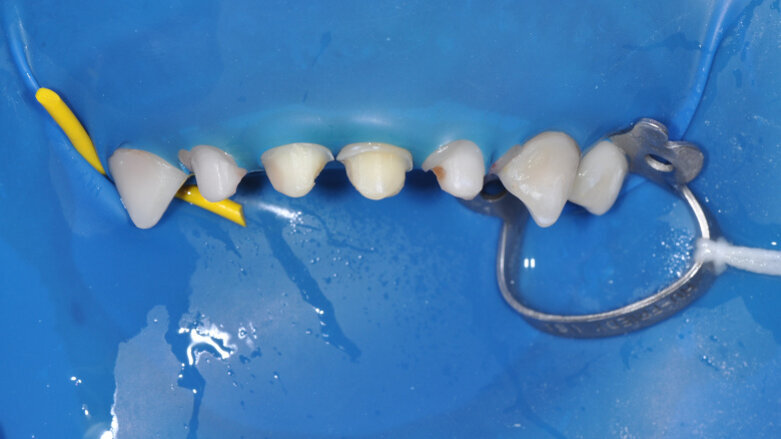

All caries was removed using a round diamond bur, and mesial and distal reduction were achieved with a fine tapered diamond bur to open the interproximal contacts and to begin circumferential reduction. Buccal and lingual reduction were achieved with a round-ended straight fissure diamond point. All margins and the extent of reduction were dictated by the caries and kept to a minimum in order to preserve as much tooth structure as possible. The margins were kept supragingival (Fig. 4).

Fig. 4: Crown preparations with margins kept supra-gingival.